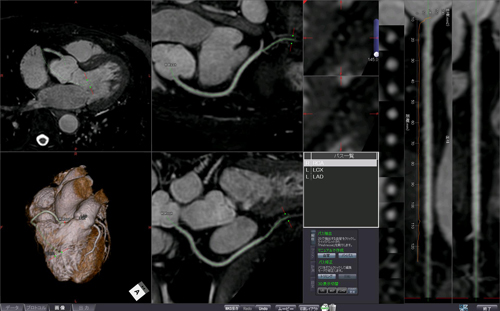

従来より定評のあるziostation2のCT冠動脈解析と同一のGUIと操作性を実現しました。簡便な操作で冠動脈のパスの抽出や修正ができるので,処理時間も短縮されます。また,血管の抽出精度がさらに向上し,複数の血管パスを利用して多曲面をMIP投影するFlex Surface MIPにより広範囲の冠動脈の観察もサポートします。

図5 MR冠動脈解析2